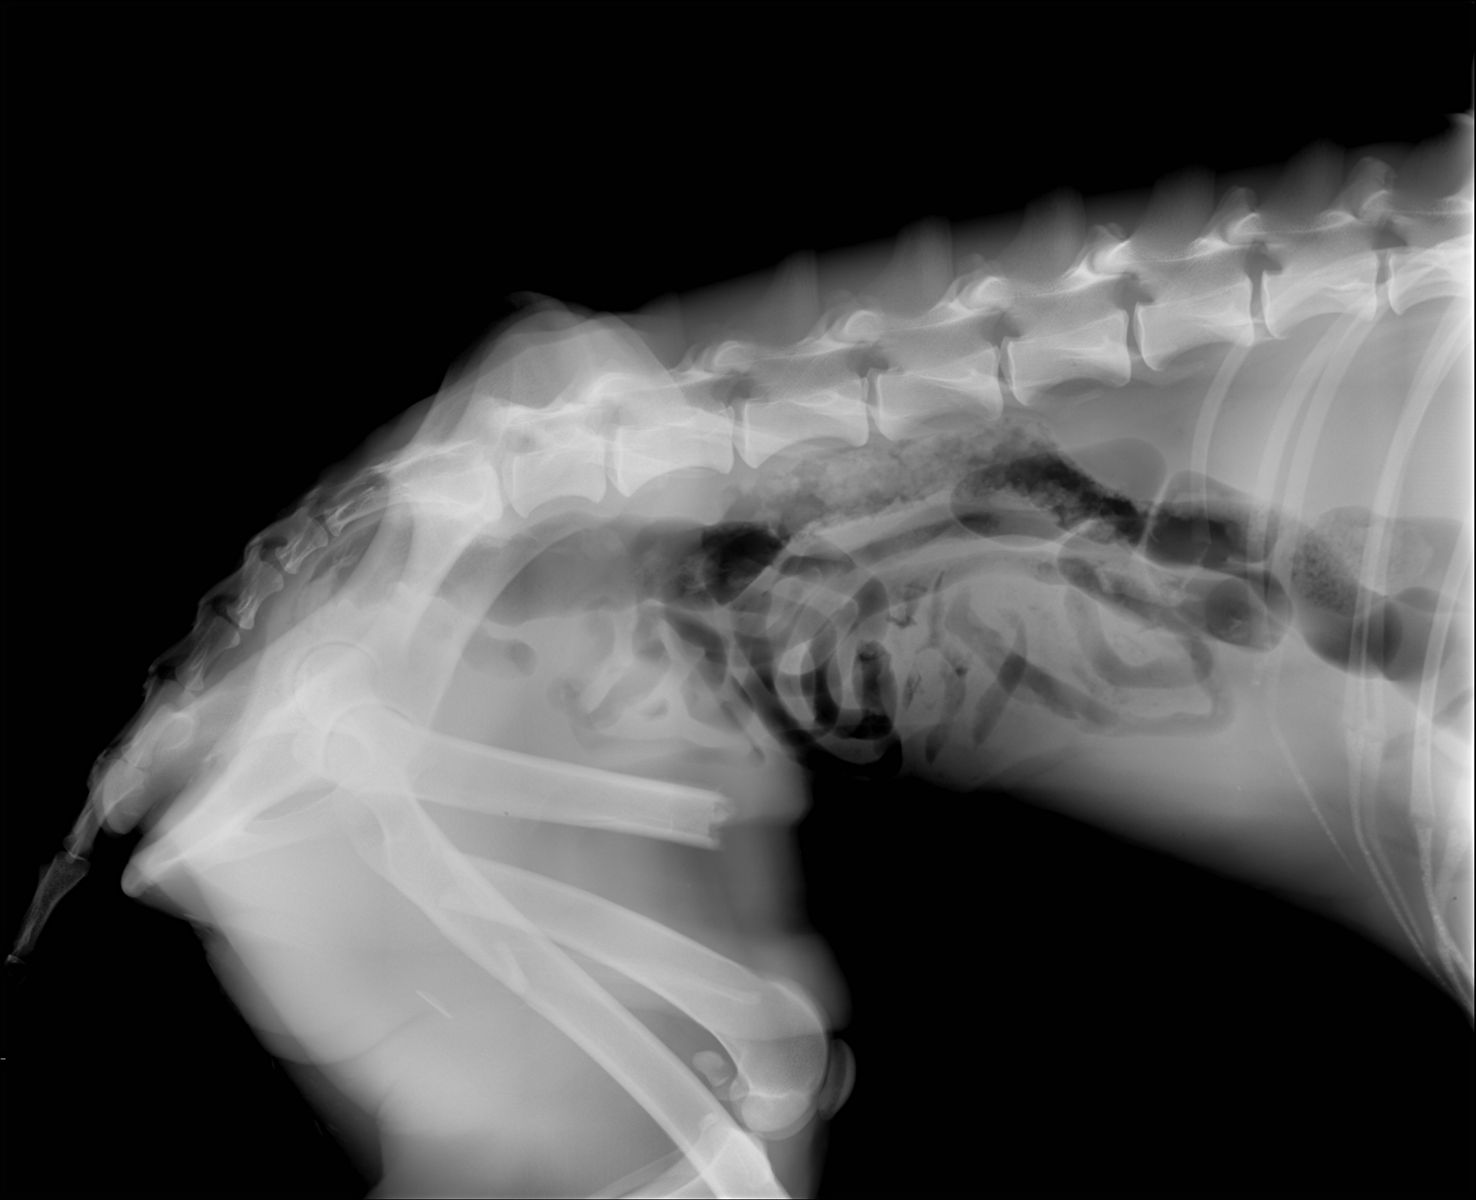

Marcus n’était plus qu’un véritable squelette, avec une fracture complexe du fémur au postérieur gauche. Il a dû vivre un véritable enfer, seul, blessé et affamé…

Il a été opéré en urgence à la clinique du refuge de la FBM, où il est actuellement en convalescence 🩺. La clinique est aujourd’hui totalement saturée, faisant face chaque jour à l’arrivée de nouveaux cas lourds : fractures, blessures graves, chiens brisés par la maltraitance et l’abandon… 😞 Malgré cette situation extrêmement difficile, Marcus a pu être pris en charge et bénéficie désormais de tous les soins nécessaires.